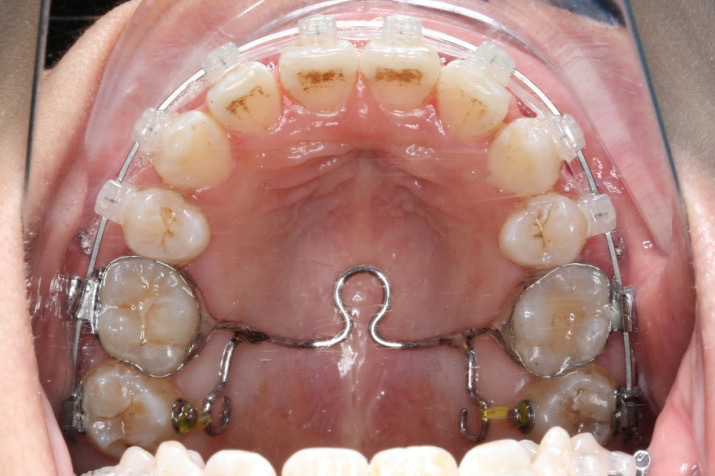

拔除14、24、34、44,上颌TPA+上颌高位支抗钉

2.第2.5个月:2017.1.13 ◆ 上颌加TPA,植入1312-08种植钉,上下0.16cu-niti

2016.10.31  初戴,0.013cu-niti2017.1.13  上颌加TPA,U56间斜形植入韩国庆北1312-08种植钉,上下0.16cu-niti

2017.02.16  上下0.014*25 cu-niti,50g 拉尖牙远中